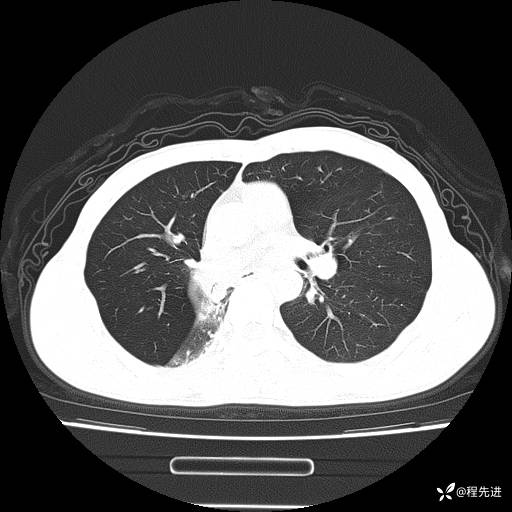

患者性别:男

患者年龄:49岁

主诉:咳嗽、胸痛1周

简要病史:1周前受凉感冒后开始出现咳嗽症状,阵发性连声咳,痰多,黄白痰,不易咳出,伴胸痛、气紧、胸闷,右侧为主,活动用力、呼吸时胸痛明显,曾在当地诊所贴敷膏药仍疼痛

体格检查:T:36.3 ℃ P:80 次/分 R:20 次/分 BP:120/88 mmHg,指脉氧饱和度97%,意识清晰,呼吸平稳,右侧第二、三肋骨压痛,可见膏药贴敷,皮肤无异常,双肺呼吸音粗,未闻及干湿性啰音。心率80次/分,节律整齐,无杂音。腹平软,全腹无压痛无反跳痛

临床诊断:社区获得性肺炎

CT平扫: